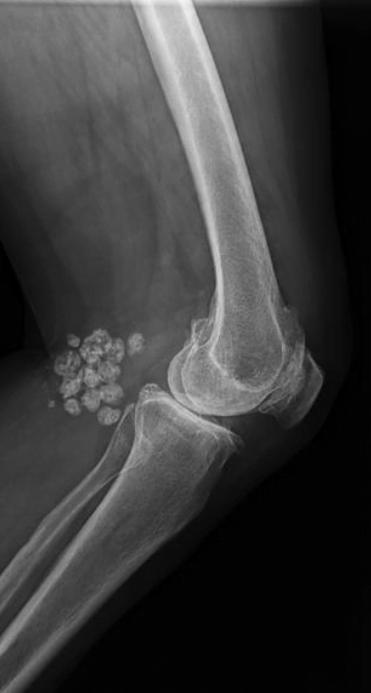

Hvis du oplever symptomer, der kan tyde på en Bakers cyste, bør du kontakte en læge. De vil sandsynligvis begynde med at stille spørgsmål om dine symptomer og foretage en fysisk undersøgelse. De kan også bestille billeddiagnostiske tests, såsom en ultralyd eller en MR-scanning, for at bekræfte diagnosen.

I nogle tilfælde kan det være nødvendigt med en aspiration, hvor en nål bruges til at trække væske ud af cysten. Dette kan både bekræfte diagnosen og lindre nogle af symptomerne.

CT scanning af baker cyste